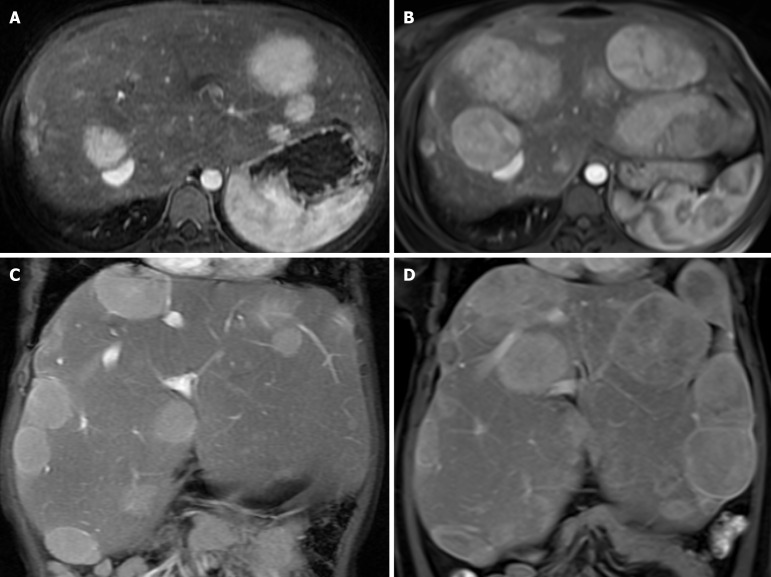

Abstract Image